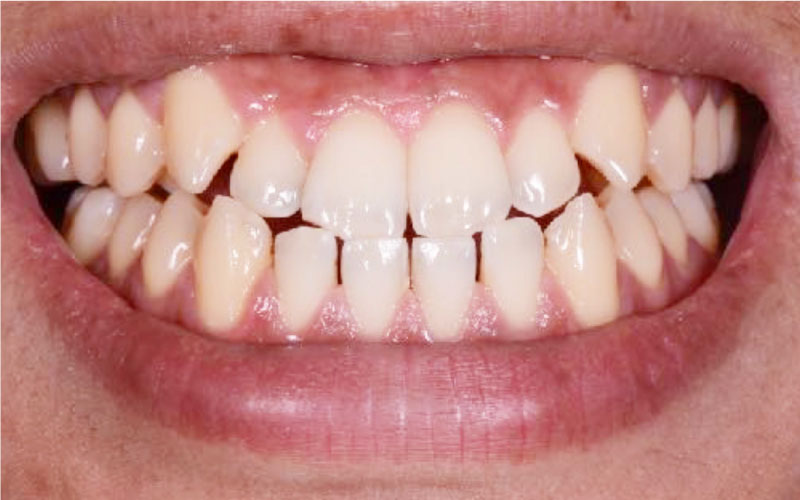

Before

• 牙齒暗黃

• 顏色不均

After

• 晶鑽居家美白

• 溫和美白不敏感

• 客製化專屬牙脫